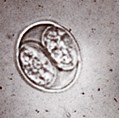

foto van een oöcyste

In de ontlasting kapselen de eieren zich vanaf twee dagen na uitscheiding in (oöcysten). Dan pas zijn ze besmettelijk. Het vervelende is dat ze heel lang besmettelijk blijven, in tuinen, parken en zandbakken waar de kat haar uitwerpselen begraaft. Zogenaamde tussengastheren zoals schapen, runderen, vogels en knaagdieren, maar ook de mens kunnen zich weer besmetten met deze cysten (via grondcontact) waarna ook een vermenigvuldiging in het lichaam plaatsvindt. In de spieren en hersenen vormen zich dan weefselcysten. Deze cysten kunnen jarenlang aanwezig blijven en zelfs na de dood van de gastheer nog lange tijd infecties veroorzaken als hiervan wordt gegeten. En wanneer katten uiteindelijk weer besmette prooidieren eten, is de cirkel rond. In streken waar geen katten voorkomen, wordt de ziekte niet bij de mens aangetroffen.